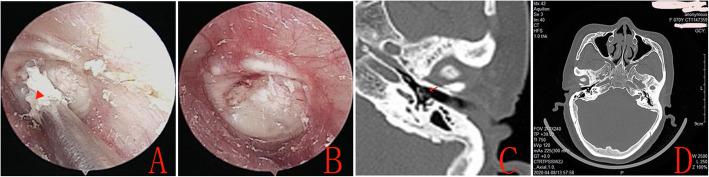

No other complications, such as iatrogenic sensorineural hearing loss, facial nerve palsy, vertigo, or tinnitus, graft lateralization or significant blunting were observed during the follow-up period in either group. Endoscopic examination found that the lateral perichondrium graft gradually formed the crust in all the patients in the Group A during the mean follow-up period of 20.2 ± 1.9 months (Fig. 4). However, only one patient (1.49%) had small keratin pearls on the anterosuperior quadrant in the double layer graft group, that was removed under endoscopy (Fig. 5). Nevertheless, CT revealed the well pneumatized middle ear, no patients developed cholesteatoma of middle ear in either group during the follow-up period.

Fig. 4.

The preoperative perforation (a), at 3 months postoperatively (b), at 6 months postoperatively (c), epithelial pearls (Red arrow) at 19 months postoperatively (d)

Fig. 5.

The removal of epithelial pearls (Red triangle) under endoscope (a), the eardrum following the removal of epithelial pearls (b), CT revealed the eardrum (Red arrow) and well pneumatized middle ear (c and d). Please note, this is the same patient as in Fig. 4